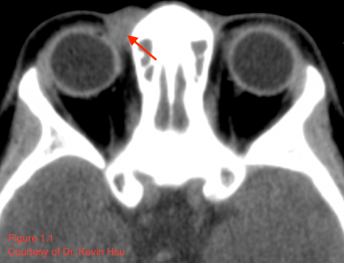

MRI can also reveal mild to moderate enhancement and calcified areas of the mass (Alkatan 2018).[2] The non-calcified portions of the tumor have a signal intensity equal or lower to gray matter on T1 weighted images, while being isointense to grey matter on T2-weighted images (Shinaver 1997).[18] In fact, the focal low-intensity areas surrounded by high-intensity areas on T2-weighted MRI have been thought to be characteristic of this neoplasm (Arora 2018).[9] MR may also reveal necrotic areas, as well as serpentine high-flow vessels which correlate to the areas of hemangiopericytoma (Murphey 2003).[8] Figure 1.2 illustrates a case of maxillary chondrosarcoma in which the lesion appeared isointense to hyperintense on T2, with a few foci of hypointensity possibly representing chondroid matrix mineralization.